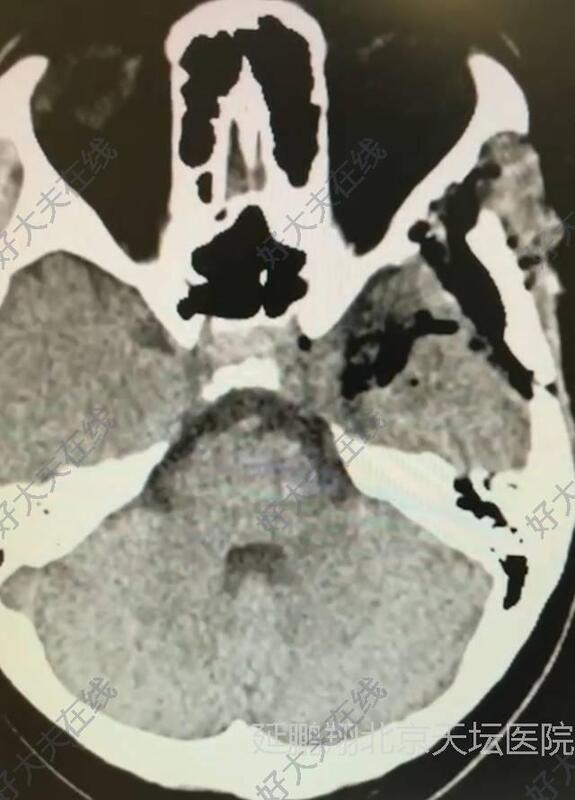

病人全麻复苏顺利,清醒后自诉左眼视力明显好转。术后六小时复查CT显示肿瘤消失,瘤腔止血满意彻底。